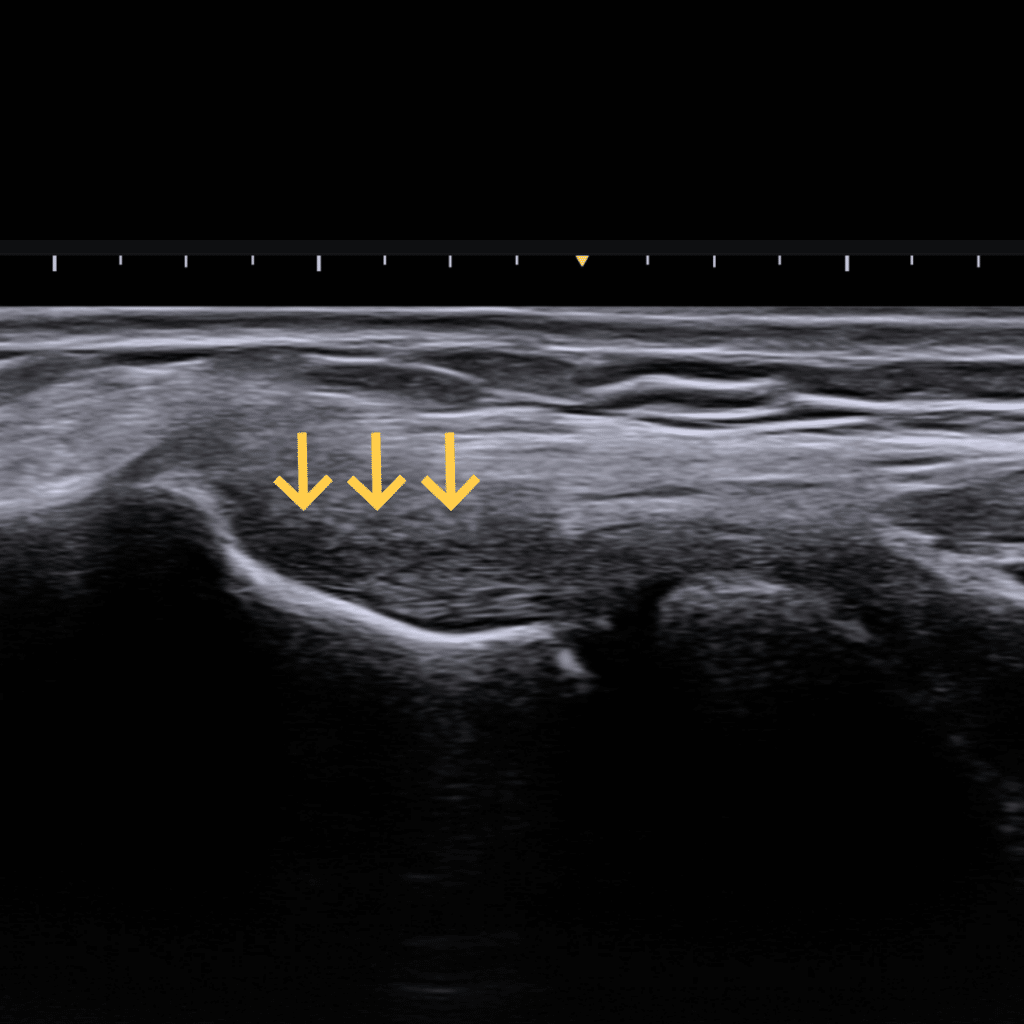

이 단계는 구조가 파괴되었다기보다 급성으로 부어있으면서 염증으로 물이 찬 상태입니다. 공격적인 자극은 피해야 합니다.

급성기를 지나 만성으로 넘어가는 과도기입니다. 힘줄 내부의 콜라겐 배열이 흐트러지기 시작하고 힘줄 자체가 붕괴되려 합니다.

장기간에 걸쳐 힘줄의 구조적 변성이 일어난 만성 상태입니다. 힘줄 곳곳에 미세 파열이나 변성된 조직(구멍)이 존재합니다. 노년층이나 오랜 기간 운동을 해온 분들에게 흔합니다.